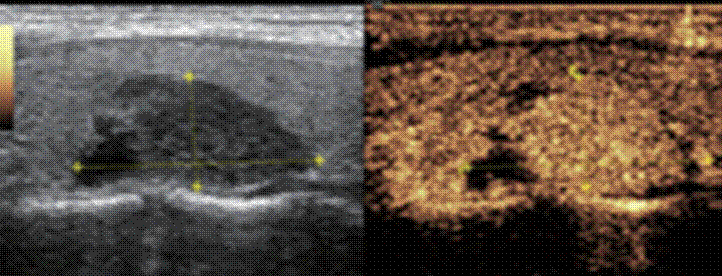

消融治疗后超声造影患者甲状腺结节完全无增强,呈坏死改变